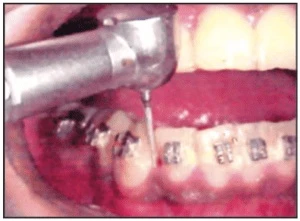

Dải kim loại mài kẽ trong chỉnh nha

Dải kim loại với các phân tử mài mòn gắn sẵn trên bề mặt. Chúng thường có một mặt không làm việc, chẳng hạn như chỉ có một mặt được gắn các phân tử mài mòn. Cây giữ dải mài kẽ được bán sẵn trên thị trường hỗ trợ cho việc sử dụng dải mài kẽ tốt hơn. Tùy thuộc vào kích thước các hạt gắn trên dải kim loại và dải mài kẽ có thể chia làm dải thô, trung bình hoặc mịn. Thường thì dải mịn được sử dụng nhiều vì nó tránh việc làm trầy xước men răng.

Hình 1A. Dải kim loại mài kẽ